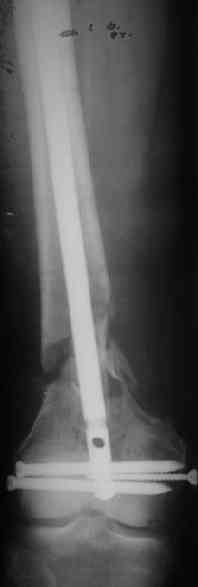

Длину восстановили, возможно, даже с изьбытком, ну да динамизируем пораньше. Введенные в овальное отверстие дистальые винты имеют угловую стабильность. Снимки приложены. Заранее спасибо за критику и комментарии.

Удалили ластину без проблем. Выявилась значительная подвижность. В этих условиях сразу пропала мотивация к постепенной коррекции аппаратом. Попробовал восстановить длину, введя между отломками spreader. Отчасти удалось. Тогда защили рану, наложили спицевой дистрактор (2 спицы в дистальный отдел и 1 вверху). после этого был убран и спонгиозный винт. И сделали антгерадное штифтование, как говорится, "по принятой в

клинике методике".